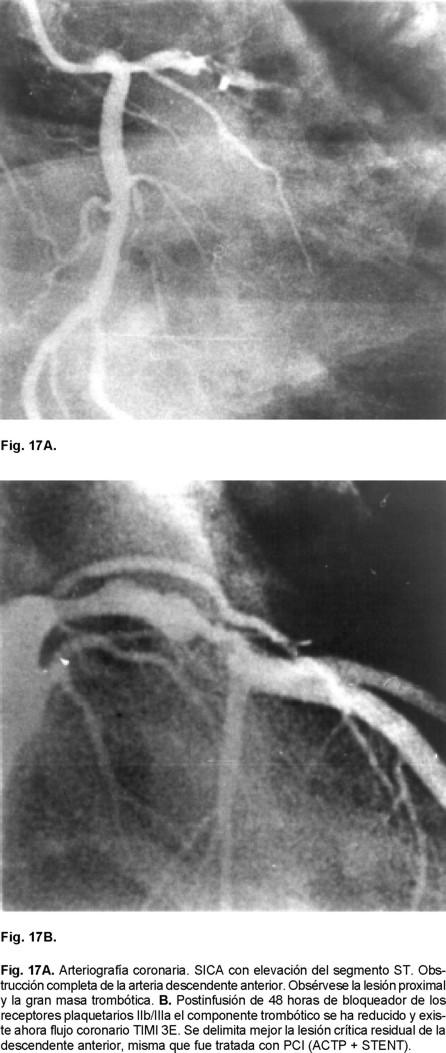

El infarto agudo del miocardio

Un problema mayor en el tratamiento del IAM es la potencialización de la masa de fibrina libre, que es eventualmente embolígena, promovida y favorecida tanto por la propia fibrinólisis endógena como la exógena (terapia trombolítica) o por la instrumentación endovascular encaminada a la reperfusión de la ARI.145 De hecho en un análisis donde se comparó ACTP vs ACTP + STENT no se demostró mayor beneficio con esta última estrategia, inclusive existió tendencia a mayor mortalidad (3.1% con balón 5.8% con STENT, p < 0.07), lo que se adjudicó a menor frecuencia de obtenerse TIMI 3E con STENT.146,147 Hecho que a su vez puede sugerir mayor grado de microembolización miocárdica. Los principales megaestudios más recientes como el CADILLAC, el ASSENT-3, el GUSTO - V y el ADMIRAL han demostrado con STENT o sin este recurso endocoronario y la administración de IRPG, flujos TIMI-3E similares sin mayor impacto en la reducción en la mortalidad del IAM con ellos, pero sí beneficio de menor trombosis aguda y subaguda del stent o de la ARI.147,148,150,151 Tal observación ha resultado hasta cierto punto decepcionante, ya que se esperaba mejor o mayor impacto benéfico sobre la microcirculación coronaria al realizarse el bloqueo plaquetario con IRP IIb/IIIa. Esto se fundamentaba en hechos tales como el haber documentado mejoría en la contracción regional e incremento en la FE con el uso de ellos.152 Tampoco en el escenario del enfermo diabético con IAM han resultado favorables, a diferencia de lo que le ocurre al diabético con SICA SEST cuando se utilizan IRP IIb/IIIa, donde el beneficio clínico es palpable.143 Se ha visto en tratándose de diabéticos con IAM o efecto nulo o mayor frecuencia de sangrados importantes (ASSENT - 3, GUSTO - V).148,150 Lamentablemente como estrategia sólida establecida de agentes antiplaquetarios sólo está la utilización de ASA que sí ha demostrado que sola o en conjunto con la terapia fibrinolítica es capaz de reducir la mortalidad en el IAM.10,11 Mas no quiere decir esto que se esté negando el efecto noble que han demostrado los IRP IIb/IIIa sobre la arteria epicárdica, pero tampoco hay evidencia sólida de que tengan mayor impacto adecuado sobre la trombosis microcirculatoria en el escenario del IAM. Hay nuevas estrategias terapéuticas que están encaminadas a la utilización de dosis menores de trombolíticos con períodos más sostenidos de IRP IIb/IIIa y que van más orientadas a tratar de obtener mejor reperfusión microvascular. Por otro lado, no podemos ignorar que no sólo es la trombosis plaquetaria la responsable de los cambios en la permeabilidad microvascular, también está incluido el papel de la cascada de neutrófilos y los efectos posibles de la propia reperfusión microvascular y de la inflamación (Figs. 2 y 3).153